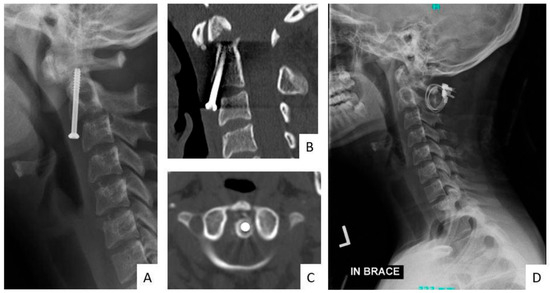

The Utility of Routine Postoperative Radiographs Following Surgical Treatment of Traumatic Cervical Spine Injuries

Background/Objectives: Postoperative cervical spine radiographs are routinely obtained during in-hospital and follow-up period. We aim to evaluate the utility of postoperative radiographs for identifying instrumentation failure and the subsequent need for revision surgery in patients with traumatic cervical spine injuries. Materials and [...] Read more.

Background/Objectives: Postoperative cervical spine radiographs are routinely obtained during in-hospital and follow-up period. We aim to evaluate the utility of postoperative radiographs for identifying instrumentation failure and the subsequent need for revision surgery in patients with traumatic cervical spine injuries. Materials and Methods: A retrospective chart review of patients who had surgical treatment for traumatic cervical spine injury was conducted. Clinical notes and radiographic reports were evaluated. Postoperative radiographs were obtained prior to discharge from the hospital, and subsequently at 2, 6, 12, 24 weeks, and 1 year. Patients who underwent revision surgery, described as any reoperation, were identified. The patients’ indications for surgery were evaluated. The results of postoperative radiographs that prompted a change in management and reoperation were analyzed. Sensitivity and specificity for postoperative radiographs were calculated. Results: A total of 295 patients were reviewed. The rate of revision surgery was 3.7% (n = 11). All 11 patients presented changes in clinical findings and physical exam, but only 3 patients (1%) were identified to have undergone revision surgery due to instrumentation failure seen on radiographs at 13, 89, and 112 days postoperatively, and none within the inpatient period. Two patients underwent revision surgery due to epidural hematoma, and six patients due to wound infection. The overall sensitivity and specificity of routine postoperative radiographs were 27% and 100%, respectively. Conclusions: Postoperative radiographs after cervical spine trauma have low clinical utility for predicting instrumentation failure in the absence of clinical findings, particularly in the inpatient period. Full article

Figure 1